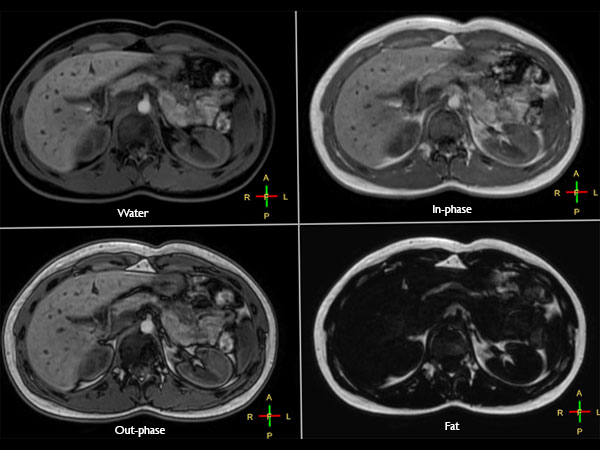

Liver imaging with MultiVane XD